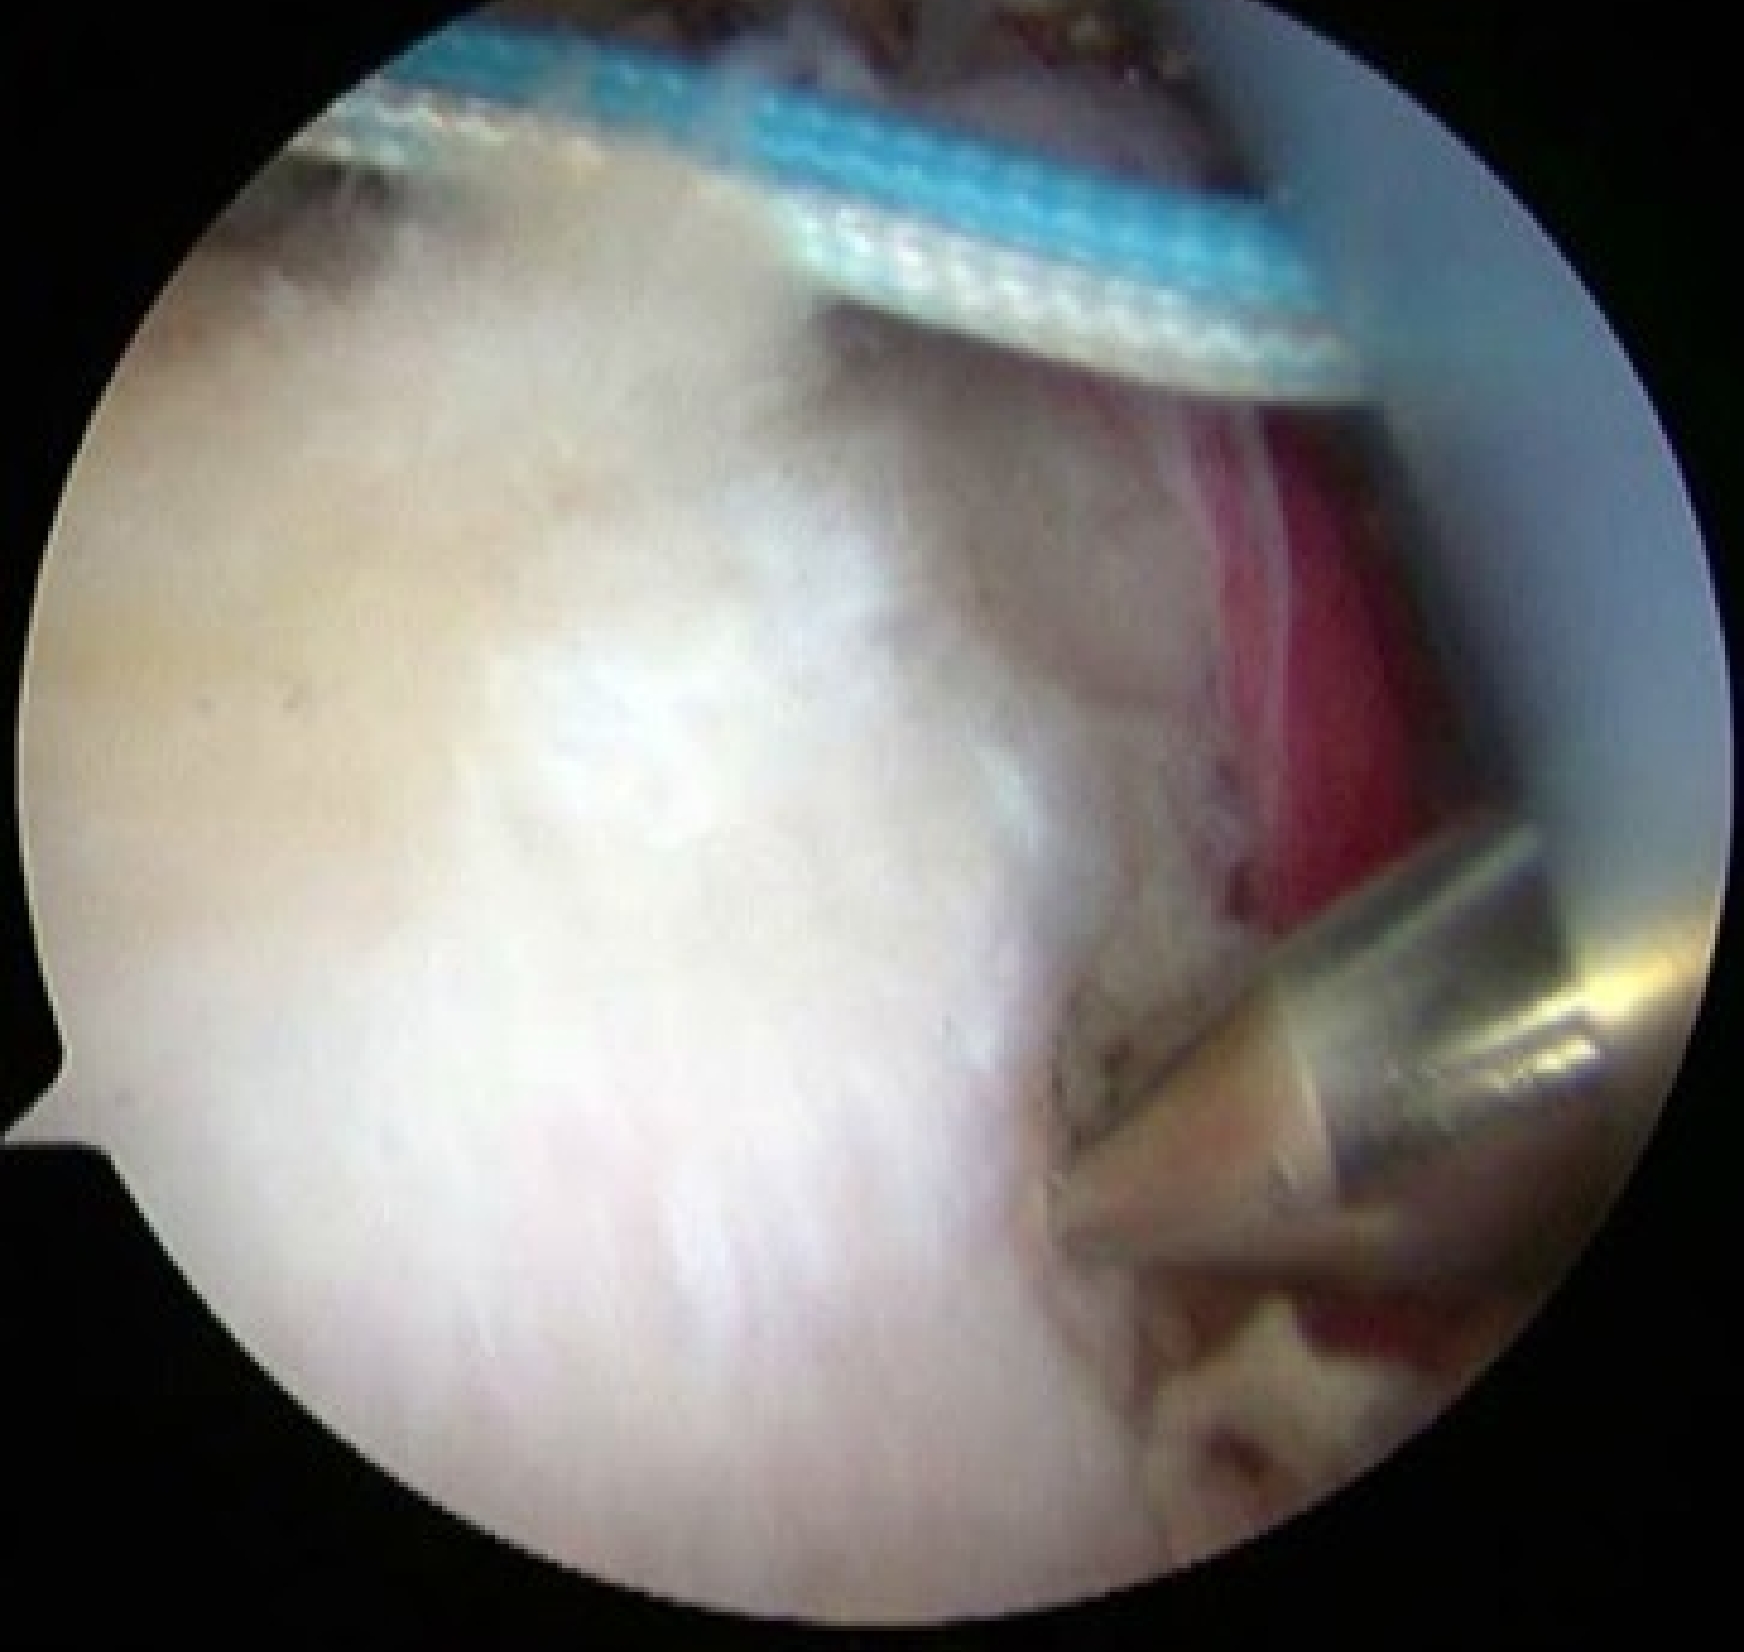

④関節唇修復

必要に応じて、上腕骨頭を肩甲骨関節窩に安定させる関節唇を修復します。